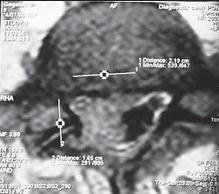

На МРТ № 17 наблюдается вентральная грыжа межпозвонкового диска в сегменте ThXII-LI с выраженными спаечными процессами на этом уровне, с вовлечением в данный процесс брюшной аорты